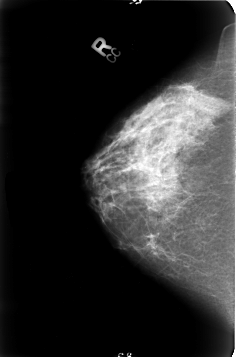

B_3023_1.RIGHT_CC

RIGHT_CC LINES 4632 PIXELS_PER_LINE 3056 BITS_PER_PIXEL 12 RESOLUTION 50 NON_OVERLAY